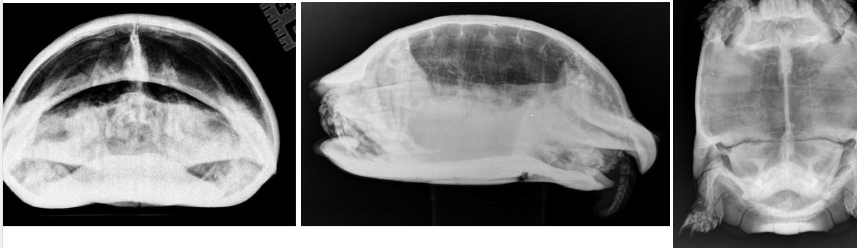

What species radiographs are these and how do they compare to rabbits

guinea pigs

vast majority of body is still abdomen, very small areas for thorax. Shared amongst hind fermenters

In which view must we take tortoise radiographs for the lungs? Can we view the heart?

cranio-caudal

lateral

not VD as shell is too thick

no we can’t view the heart due to shell